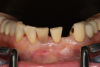

Case 3. TRAUMA: SINGLE Central INCISOR-GUIDED Smile

A 23-year-old man reported to the dental practice on January 3. Apparently, while on vacation and celebrating the New Year, the patient experienced a loss of equilibrium and found himself horizontal in the crosswalk. When surveying the damages, his friends noticed he was missing tooth No. 8. Those who were involved were not able to find the missing maxillary central incisor. The young man was eventually seen about 3 days after the trauma. A CBCT radiograph, study models, and photographs were collected, and teeth Nos. 6 through 10 were immobilized with composite and 20 x 20 orthodontic wire (Figure 14). The CBCT and photos were emailed to the dental laboratory, and the analog intraoral impression with a centric occlusion bite registration was sent via ground transportation. Due to the nature of the trauma, the laboratory and the author expeditiously converted the analog diagnostics and merged all the patient's data sets to develop the plan. Based on the 3D data sets, the laboratory and the dentist were able to accurately assess the volume of bone and soft tissue remaining after the trauma. The volume was still intact and soft tissue was plentiful (Figure 15 and Figure 16).

Fig 14. Immobilization splint placed 3 days after trauma.

Figure 14